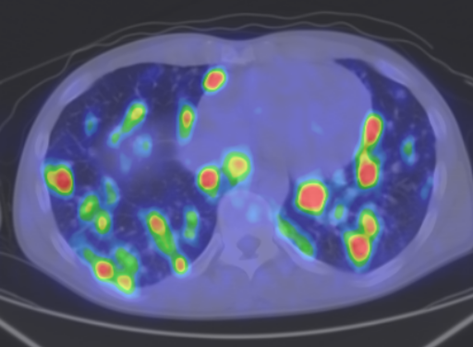

Among the general characteristics of isotope examinations, besides the ability to gain functional information, it is important to mention that – derived from the tracer principle – the examinations are highly sensitive, so the pathological processes can be detected at an early stage. SPECT is able to detect nano-molar radiotracer concentrations, while PET picks up signals coming from pico-molar radiopharmaceutical quantities. The higher sensitivity is due to the fact that functional alterations of metabolism usually precede detectable morphological changes of the tissues, thus functional studies allow earlier and more precise diagnostics. Another aspect of higher sensitivity is that in an optimal scenario, the biologic contrast between normal and pathologic function is very high. Therefore, signal intensity of a normal tissue process will be much lower than that of a pathologic one, making them easily distinguishable on the image. (Figure 2.)

Test iframe

2. FDG PET Maximum Intensity Projection (MIP) image. There is a large biological contrast between the normal and the pathologic tissues. Right sided breast cancer, ipsilateral metastatic lymph nodes and multiplex metastases in the lung. Physiologically elevated FDG uptake is seen in the brain, salivary glands, tonsils, liver and the spleen as well as in the bone marrow and at certain segments of the intestines. Also, there is increased FDG activity in the kidneys and the urinary bladder due to excretion.